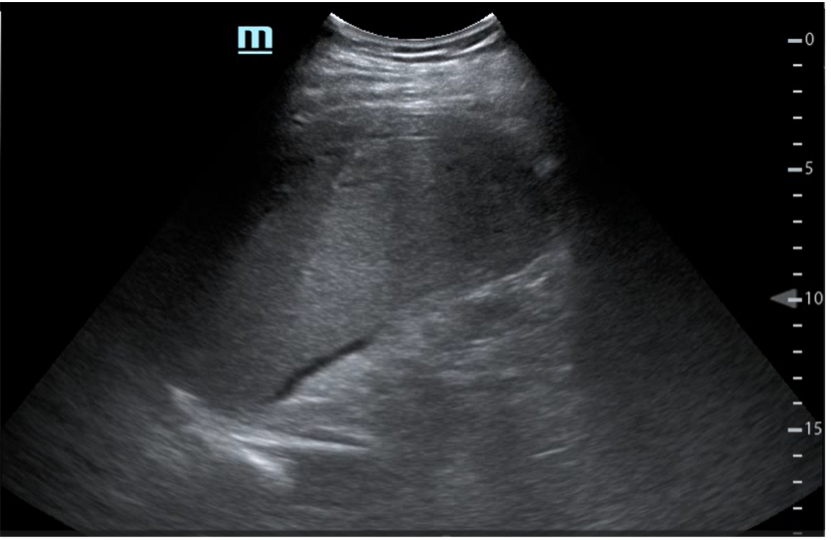

EF: Mal estado general, palidez mucocutánea, sudoración profusa. Intolerancia al decúbito supino con postura antiálgica. Abdomen: doloroso a la palpación difusa con defensa abdominal generalizada. Se realiza ecografía clínica a pie de cama objetivando líquido libre abdominal.

Paciente con cuadro de abdomen agudo ante hallazgos en ecografía clínica y anemización se solicita TAC abdominal para completar estudio. Ante diagnóstico de hematoma subcapsular esplénico y hemoperitoneo sin sangrado activo, ingresa para control del dolor y seguimiento clínico sin necesidad de intervención quirúrgica. Se solicitan serologías resultando negativas.

En este caso se pone de manifiesto la gran utilidad de la ecografía clínica a pie de cama para el enfoque diagnóstico y manejo de un paciente en urgencias.